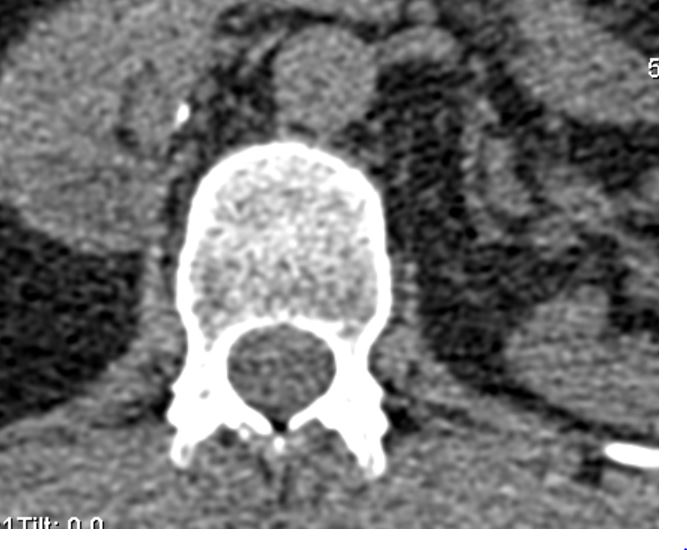

I forgot… There is no right kidney.. its been removed! My spine is bolted together with nuts and bolts, my bionic bladder is connected to a battery implant as is my spine…. batteries implants screws bolts ooops. Oops. The poor radiologists will be peering at their screens baffled and confused. The report might be muddled!!